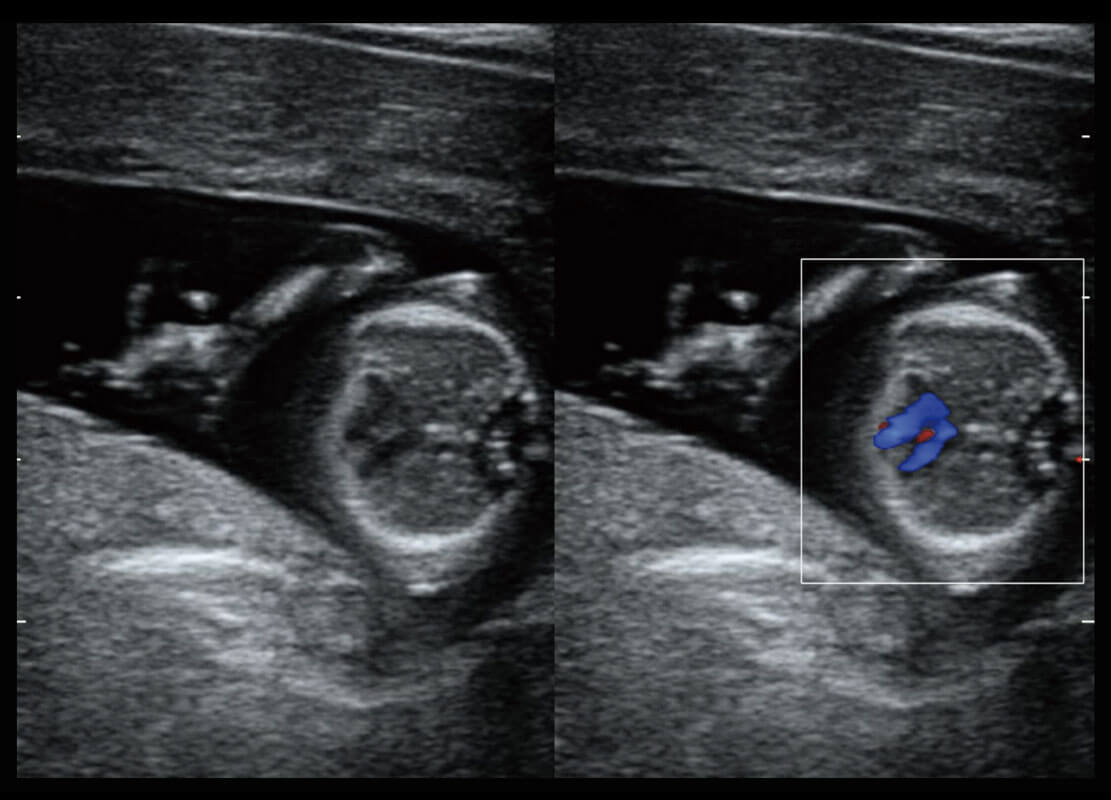

胎心筛查

P60搭载一系列胎儿心脏成像技术,实现更精细的胎儿心脏评估。

• 四腔切面

• 四腔心血流

• 右室双出口

• 胎心容积成像